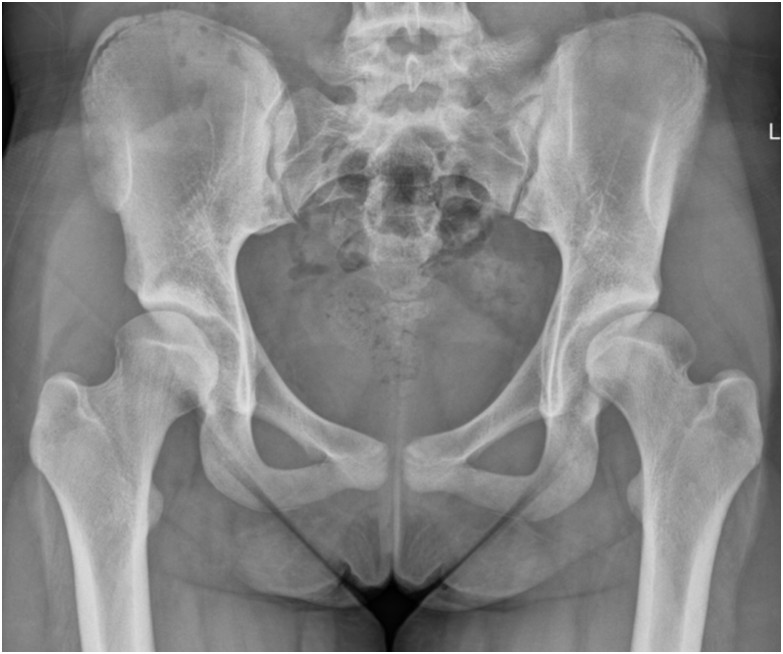

29-letnia chora skarży się na bóle w lewej pachwinie. Lekarz w badaniu stwierdził bardzo dobrą ruchomość obu stawów biodrowych. W lewym stawie biodrowym wykazał bolesność w pachwinie w czasie wykonywania jednoczesnego ruchu zgięcia, przywiedzenia i rotacji wewnętrznej. Na zdjęciu stwierdzono dysplazję lewego stawu biodrowego z jego decentracją i kątem Wiberga 10°. Wskaż dalsze postępowanie:

Pytanie 35